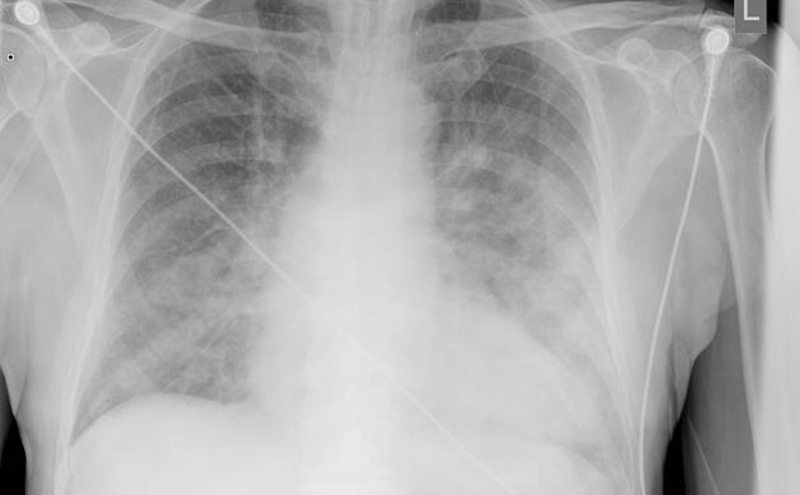

In terms of imaging, chest x-ray is a practical imaging modality to assess for SIPE. Radiographs may demonstrate signs of pulmonary edema such as cephalization of pulmonary vessels, loss of vascular definition, peribronchial cuffing, and Kerley B lines. Airspace opacities and pleural effusions may also be appreciated. It should be noted that there are cases of SIPE with a normal chest x-ray.4 Additional imaging modalities may include ultrasound or computed tomography (CT), which both are very sensitive in visualizing pulmonary edema or pleural effusions.4

Radiograph demonstrating pulmonary edema.

Radiograph courtesy of Dr. Jeremy Jones, Radiopaedia.org, rID-6463